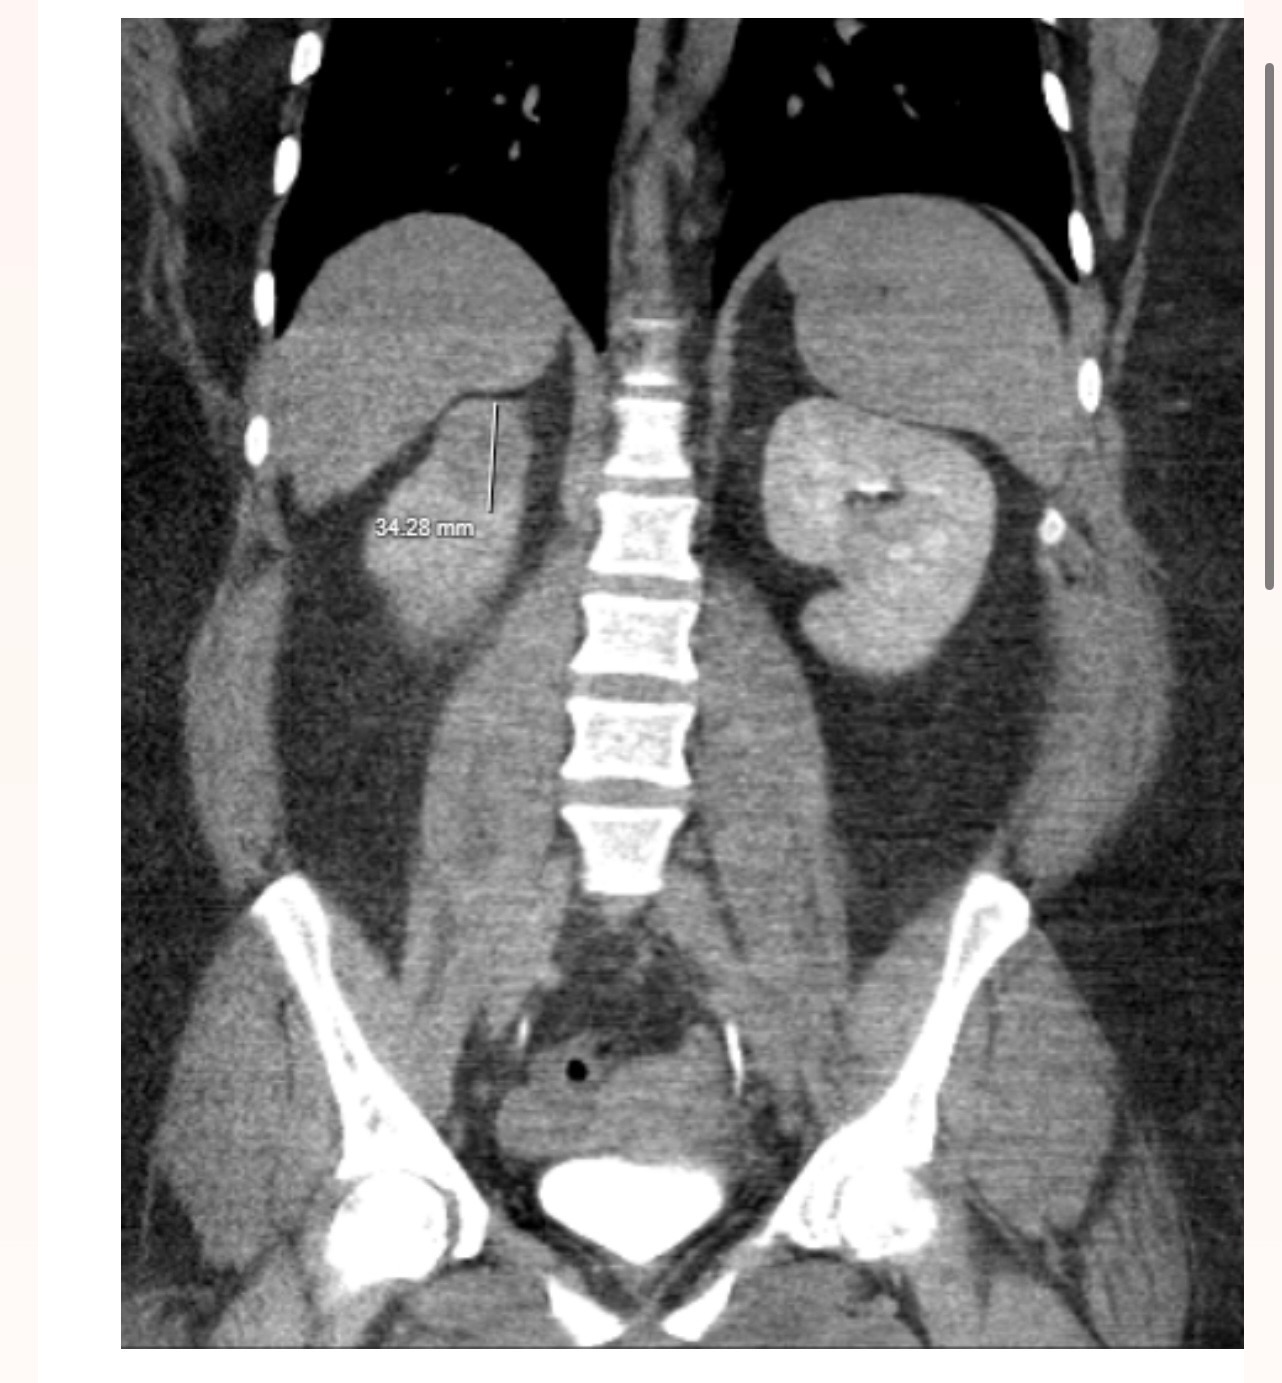

My daughter is facing one of the most difficult times of her life. She was recently diagnosed with Renal Cell Carcinoma, a form of kidney cancer, and just as we were coming to terms with this devastating news, she lost her job and her medical insurance. The doctors have told us that she needs life-saving surgery in just two weeks, but without insurance, the costs are overwhelming.